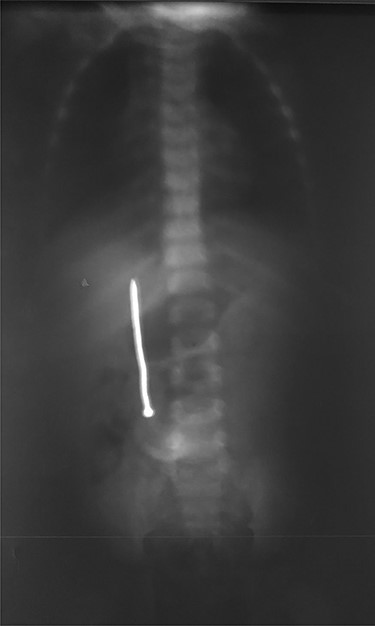

Abdominal examination was normal. A repeat abdominal radiography was done. The nail’s position had not changed from the first X-ray site, with no free peritoneal air (Fig. 2).

Plain radiography plays the main role both in the diagnosis and the choice of operative interventional moment—either by pinpointing the radio-opaque image, or by showing certain FB characteristics, or by noting images suggesting complications (absent in our case), or even by projecting the FB in the same place over a period of time, an aspect inductive of fistula. In our case, right-edge superposition of the FB image upon the lumbar spine is characteristic of FB positioning in the second part of duodenum [5, 6]. Its persistence in the same place (the second part of the duodenum as in our case) suggests the presence of a duodenal fistula or perforation, which requires surgical intervention [7].